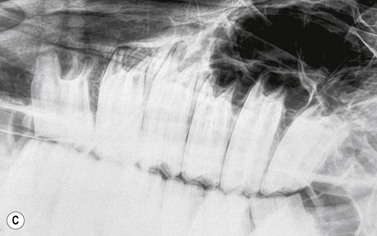

Contrast studies

Placement of a radio-opaque marker over an area of facial swelling and repetition of a radiographic projection (Fig. 13.21) can be an invaluable aid when assessing the clinical significance of radiographic changes. If a cutaneous draining tract is present, as is common in cases of periapical infection of the mandibular cheek teeth or upper 06s and 07s, a blunt metallic probe can be placed into the tract, held in place with tape (Fig. 13.22) and a repeat radiograph taken (Fig. 13.23). This very simple form of contrast study often provides unequivocal evidence that a tooth is infected.

image

Fig. 13.21 Lateral oblique radiograph of the hemimandible of a horse which presented with a swelling on the ventral aspect of its mandible. A radio-opaque marker has been taped to the area of maximal facial swelling, which corresponds to an area of clubbing (short, rounded appearance) of the caudal root of the 08 due to loss of the apex of that root and surrounding radiolucency.

image image

Fig. 13.22 (A & B) A blunt metallic probe placed into a cutaneous discharging tract and secured with radiolucent tape can provide strong evidence as to which tooth is infected in cases of suspected periapical infection.

Fig. 13.23 Lateral oblique radiographs with a blunt metallic probe in place in cases of periapical infection with discharging cutaneous tracts involving the mandibular (A) and rostral maxillary (B) cheek teeth.